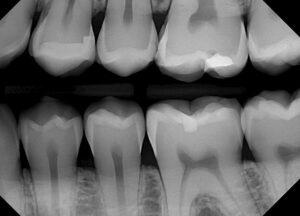

”Bitewing

Bitewing X-rays are commonly used to detect decay between the teeth and assess the health of the supporting bone. By capturing detailed images of the upper and lower teeth in a single view, bitewing X-rays enable early detection of cavities and periodontal disease.